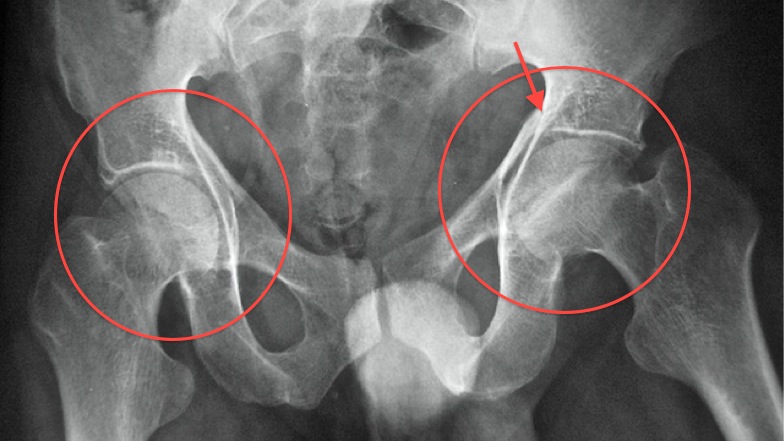

Рентген ТБС: Нормальные показатели

Раздел: Необычные решения